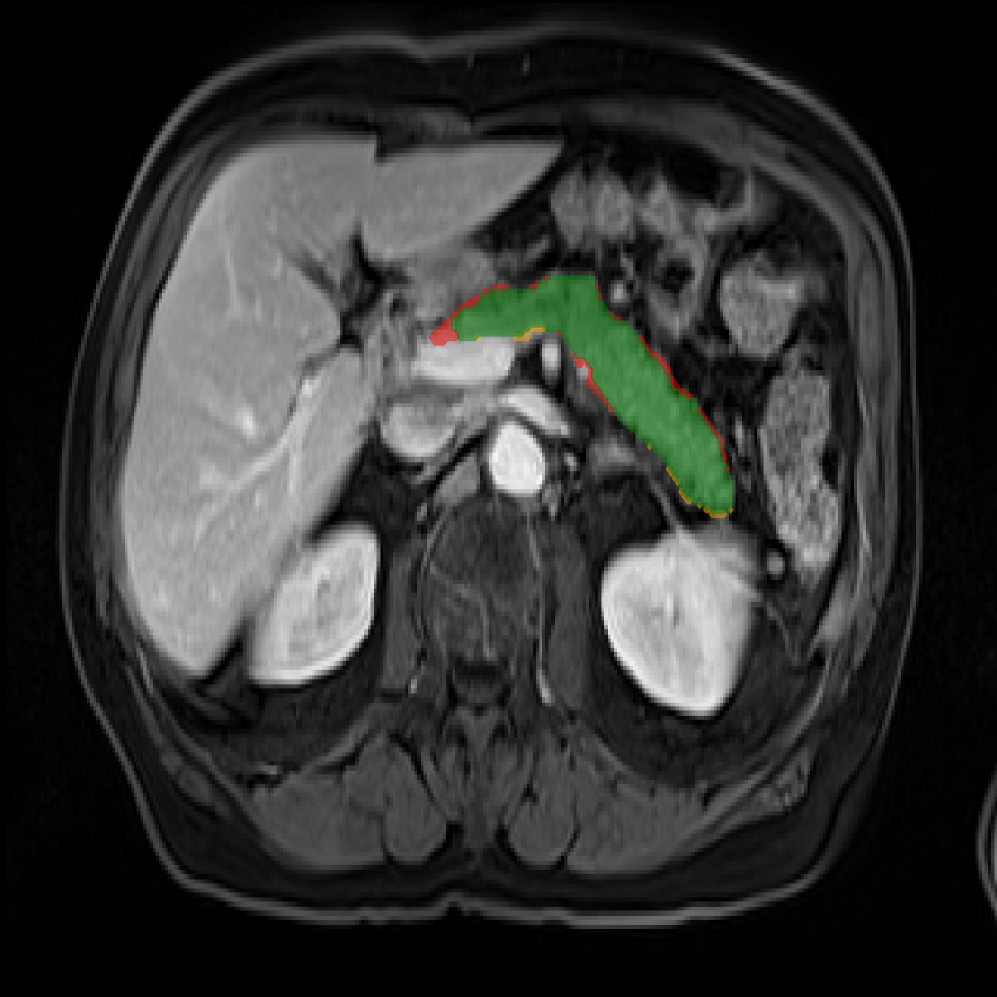

Accurate pancreas segmentation is a critical prerequisite for precise cyst analysis and classification. Recently, we developed PanSegNet [zhang2025large], a novel segmentation architecture incorporating linear self-attention layers [zhang2022dynamic] within the nnUNet framework [isensee2021nnu] to enhance global information modeling capabilities while maintaining computational efficiency (Fig. 1). PanSegNet demonstrated exceptional segmentation performance across both T1W and T2W modalities, achieving mean dice scores of 86.817.30% and 89.626.38%, respectively (Table 1, Fig. 2b-c). This performance significantly exceeded that of Swin-UNETR [hatamizadeh2021swin], one of the most used state-of-the-art transformer-based medical segmentation models, which achieved dice scores of 79.091.40% and 76.290.66% for T1W and T2W, respectively (). In this study, we integrated PanSegNet into our Cyst-X engine along with a classifier for risk prediction. In Section 2.2, we show that the choice of segmentation model affects the classification results. The performance advantage of PanSegNet was consistent across all seven medical centers, demonstrating robust generalization despite variations in imaging protocols and equipment (Table 1). This cross-institutional reliability is particularly important for clinical applications, where model performance must remain consistent regardless of imaging site or acquisition parameters.

Each patient was categorized into one of these three ground truth classes: no risk/control, IPMN low-risk, or IPMN high-risk. To evaluate variability in image acquisition, we applied uniform manifold approximation and projection (UMAP) to image quality indicators, revealing distinct clustering patterns by imaging center and slice thickness. This heterogeneity reflects real-world clinical variability, enhancing the dataset’s generalizability while presenting technical challenges for model development. Fig. 6 shows examples of low-grade, high-grade, and cancer developing IPMNs from the Cyst-X dataset.